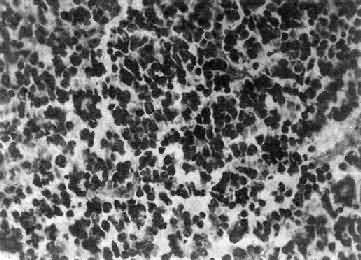

肉眼观,组织呈鱼肉状,色灰红。镜下,肿由圆形、椭圆形或胡萝卜形细胞构成,胞核着色深,胞浆少而边界不清楚,有多少不等的核分裂像。细胞密集,间质中有纤细的纤维,血管不多。细胞环绕一个嗜银性纤细的神经纤维中心作放射状排列形成典型的菊形团(图16-26),这对髓母细胞的病理诊断有一定的意义。细胞具有向神经元及神经胶质双向分化的潜能,既能向神经母细胞、节神经细胞分化,也能向胶质母细胞、星形胶质细胞分化。如细胞侵入软脑膜,可在蛛网膜下腔脑脊液中广泛播散转移。

图16-26 髓母细胞

细胞较小,着色深,密集排列,有菊形团形成